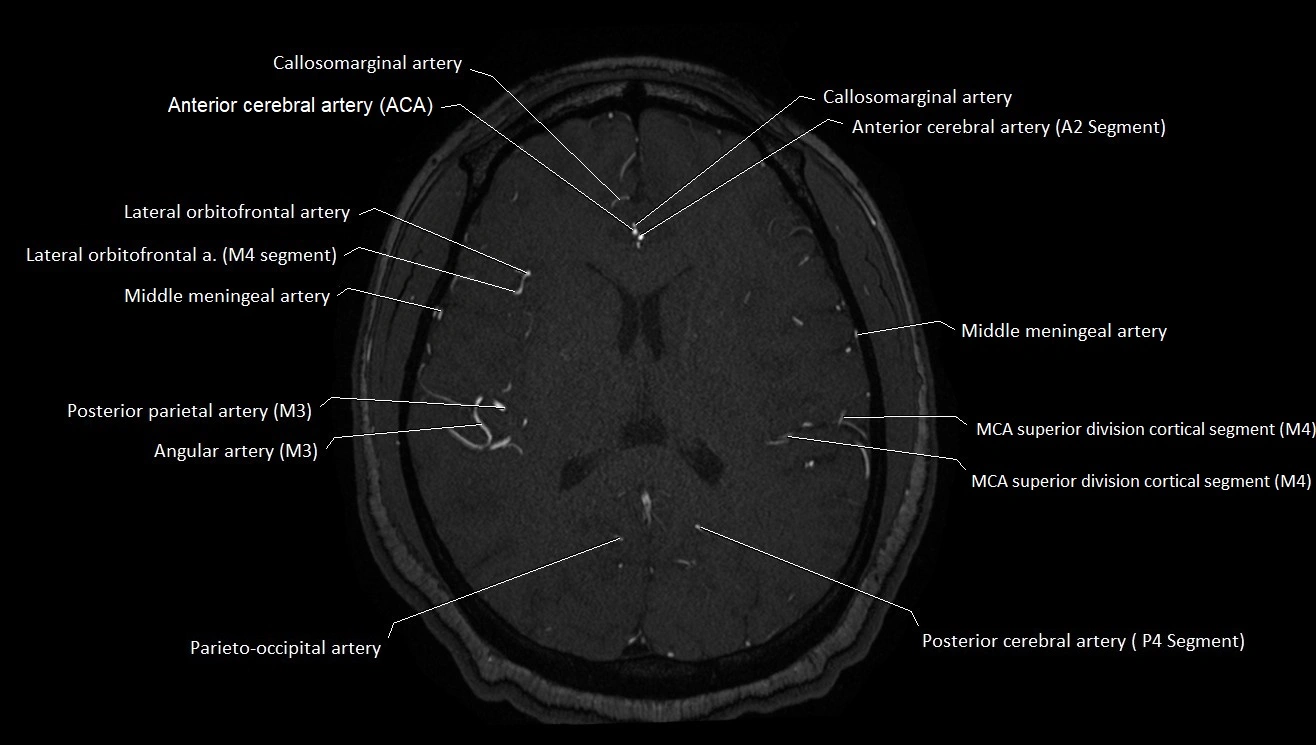

MRI images

image